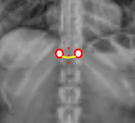

Apical Vertebral Rotation (AVR) - Nash-Moe classification